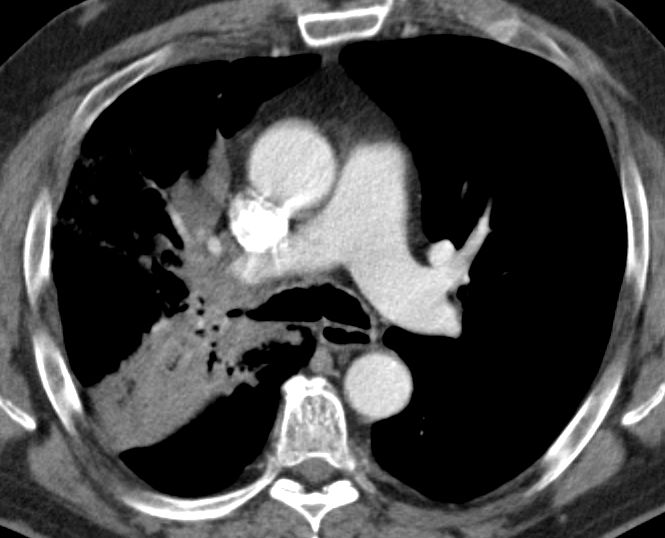

blauer Punkt   56-jähriger Mann mit einem Adeno-Ca des rechten Mittellappens. Im CT große Raumforderung im rechten Hilus. Das PET-CT zeigt, dass der eigentliche Tumor unterhalb der Raumforderung sitzt.